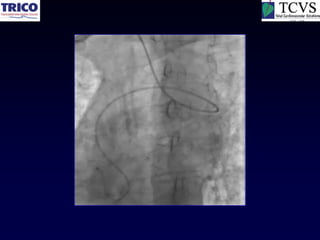

Another example

Catheter Knot

Reduction